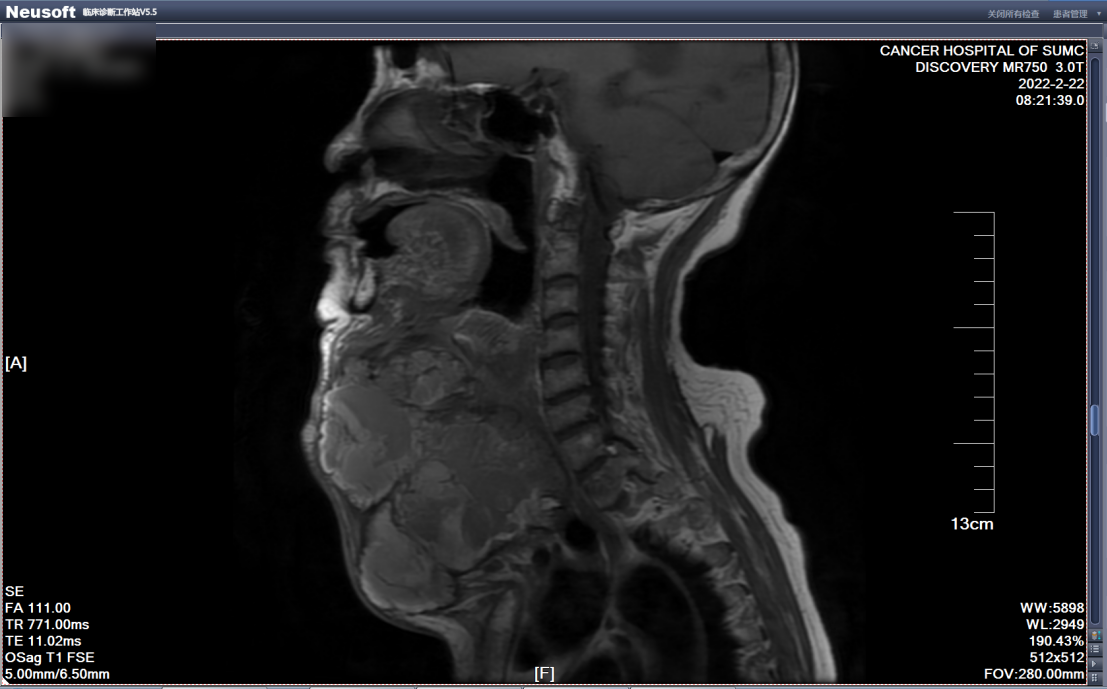

经入院检查发现,患者颈前区巨大团块肿物大小约20×18×12cm,质硬,界不清,表面皮肤可见破溃出血,范围大小约3.0×3.0cm。入院后予完善相关检查,患者磁共振检查提示:甲状腺多发结节、肿块,考虑结甲性甲状腺肿并恶变,右颈多发淋巴结肿大。

磁共振图像